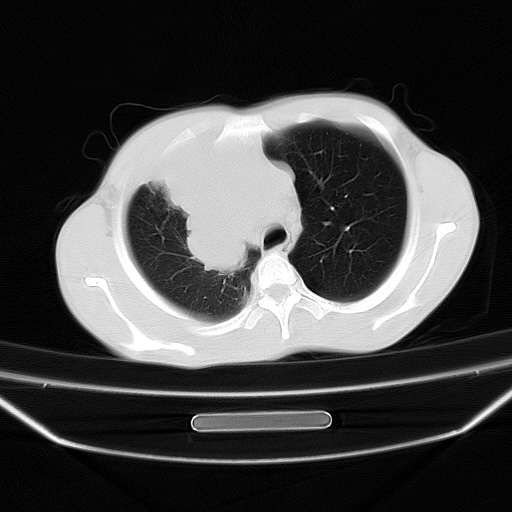

以下是引用zjzjr在2008-7-20 12:57:00的发言:[br]考虑为生殖源性肿瘤(内胚窦瘤),侵袭性胸腺瘤可能性大;右侧少量胸腔积液。

以下是引用xinliheng001在2008-7-20 21:17:00的发言:[br]右纵隔巨大分叶状软组织均质密度肿块,右上肺叶受压明显,纵隔右移、胸膜受累有少量积液和结节样增厚。应增强扫描一定会有更具诊断价值的信息。

以下是引用xinliheng001在2008-7-20 21:17:00的发言:[br]右纵隔巨大分叶状软组织均质密度肿块,右上肺叶受压明显,纵隔右移、胸膜受累有少量积液和结节样增厚。应增强扫描一定会有更具诊断价值的信息。